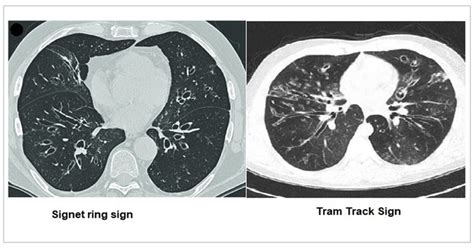

Figure 1. Computerized tomography (CT) findings.

Bronchiectasis HRCT Signet Ring

Bronchiectasis Tram Track Sign